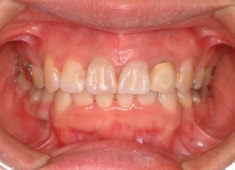

治療後(3年2ヶ月後)